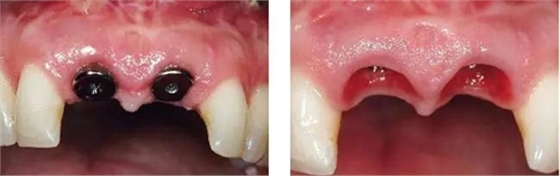

圖11、穿黏膜愈合1周后,牙齦外形良好。

圖12、種植體植入后2個月取出愈合帽,可見牙齦外形和齦乳頭維持得相當好。

圖13、安放全瓷基臺。